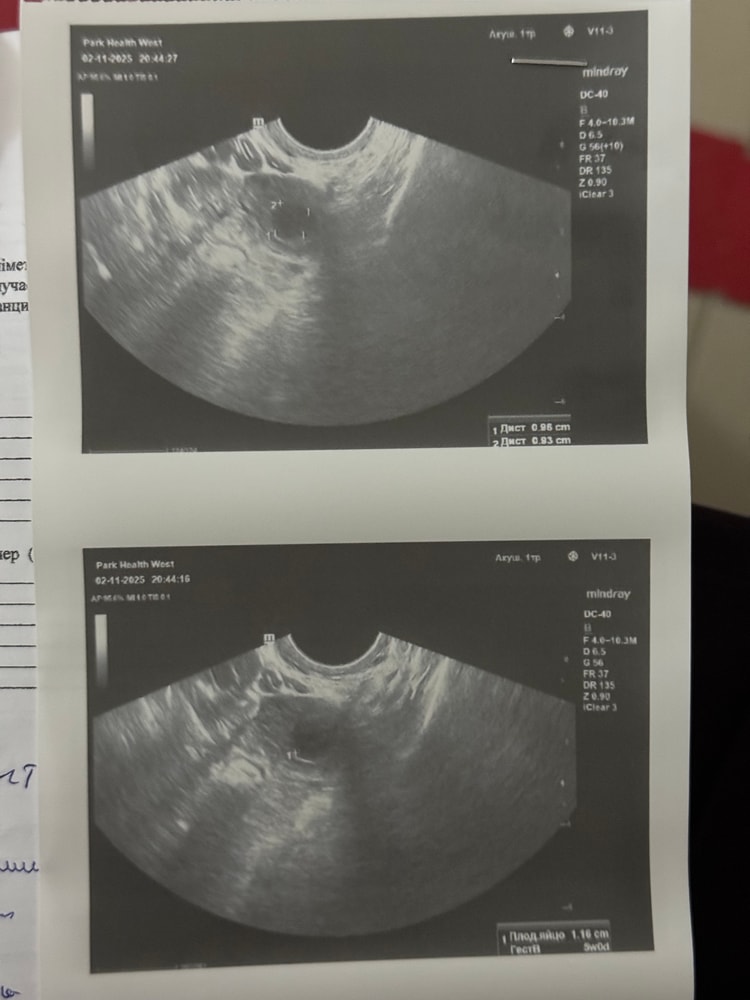

Сегодня 4 день задержки. Белым отмеченный тест сегодняшний(примерно в 11 утра проверяла) остальные до 30.10 проверенные. Примерно в 7 вечера заметила светло коричневые выделение в мааалом количестве. Сразу вызвали скорую. В больнице сначало осмотрели по узи. Написал есть подозрение на внематочную беременность с левой стороны. Но там мне не больно. Меня беспокоит только поясница чуток. Потом гинеколог на кресле осмотрела. Сказала что матка увеличена. На внематочную подозрении у меня нет, наверное в пути к матке сказала гинеколог. Акушерский срок 5н3д. Эмбриональный на 2 недели примерно меньше будет же. Что думаете?

Тесты полосят, значит, пя уже прикрепилось, на УЗИ пя видно же, не описывают, где оно?